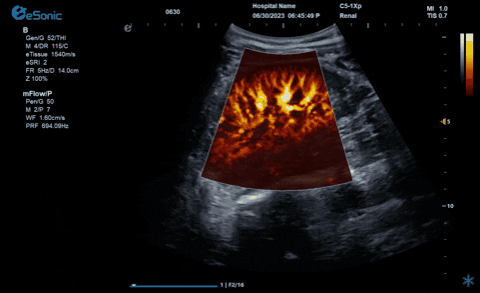

3377体育医疗的eHertz系列彩色多谱超声诊断系统凭借强大的RawVision?原数精准平台和SDBeam?软波声束合成技术推出专属的mFlow ?超微血流显像技术,该项技术可专用于极低速血流成像。彩色多普勒血流(CDFI)检查时,通常会将滤波器的频率设置为大约50hz,并随时调整标尺和增益,以便在背景噪声发生前显示小血管......